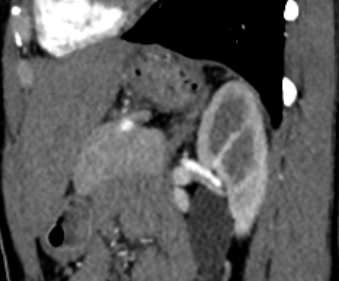

Мультиспиральная КТ сосудов почек (КТ-ангиография) с внутривенным болюсным контрастированием проводится для диагностики патологии почечных артерий. С помощью КТ-ангиографии можно выявить врожденные аномалии развития сосудов почек, диагностировать стенозы (уменьшение просвета) почечных артерий за счет развития атеросклеротических бляшек.

КТ сосудов почек применяется для выявления признаков вторичной артериальной гипертензии, при планировании оперативных вмешательств и для оценки успешности проведенной операции на сосудах. КТ ангиография почечных артерий позволяет оценить их анатомию, выявить добавочные и аберрантные почечные сосуды, определить типично ли они распространяются в ворота почки или заходят в паренхиму через корковый слой.

Чувствительные детекторы улавливают рентгеновские лучи после их прохождения сквозь тело человека. На основании этих данных получаются изображения сосудистой системы почек в мельчайших подробностях. Кроме того, с помощью цифровой обработки данных томограф реконструирует трехмерные модели кровеносных сосудов на уровне исследуемой области. 3D-реконструкции помогают увидеть пространственное соотношение анатомических структур и значительно повышают качество диагностики.

В наших медицинских центрах КТ-ангиография почечных артерий выполняется на новейших мультиспиральных компьютерных томографах экспертного класса TOSHIBA AQUILION. Аппараты сканируют область почек, производя одномоментно множество послойных срезов исследуемой зоны, благодаря этому создаются изображения кровеносной системы высокого качества. Это позволяет проводить точную и достоверную диагностику патологии почечных артерий. При этом за счет скоростного мультисрезового сканирования пациент получает минимальную дозу рентгеновского облучения.